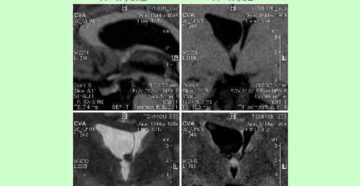

Узи лимфоузлов шеи и в подмышке: что показывает и как проводится Эндокринолог высшей категории Анна…